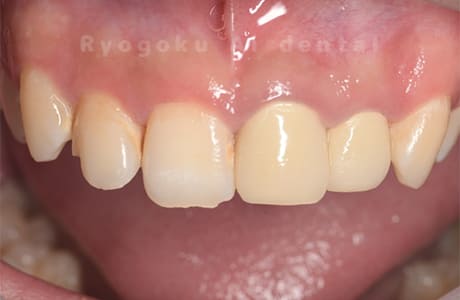

前歯の腫れが治らない、とのことでご来院された患者様です。前歯には他院で自費で入れた被せ物が入っており、被せ物のやり変えと共に根管治療の提案を致しましたが、このままの状態での治療を希望されたため、歯根端切除術を行いました。手術後の痕も気にならずに、腫れもなくなり、非常に満足して頂きました。半年経過を追っておりますが、現在も再発等ございません。

<リスク・副作用>

外科手術のため、術後に出血、痛みや腫れ、違和感を伴います。口腔内の状態によっては適応できないことがあります。歯根端切除で治らなければ抜歯を検討しなくていけない場合もあります。